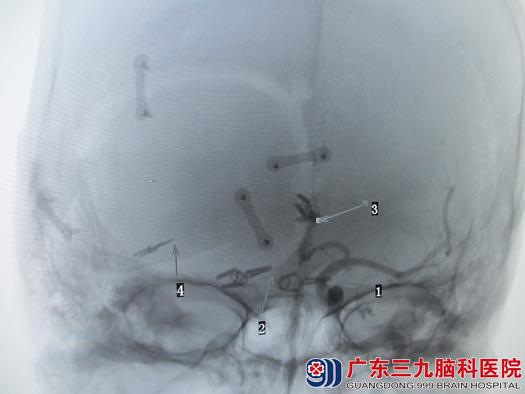

考虑介入治疗不能一次性栓塞完全,且费用较大,家属选择手术治疗。由于破裂动脉瘤为右侧后交通动脉瘤,鲁明主任主刀在全麻下行右侧翼点入路双侧后交通、右侧大脑中动脉、右侧大脑前动脉多发动脉瘤开颅夹闭术,术中显微镜下成功一次性夹闭四个动脉瘤,术中出血少,经过顺利。术后朱女士恢复很快,复查DSA提示动脉瘤夹闭完全,载瘤动脉完好,康复出院。

术前CTA

术后造影